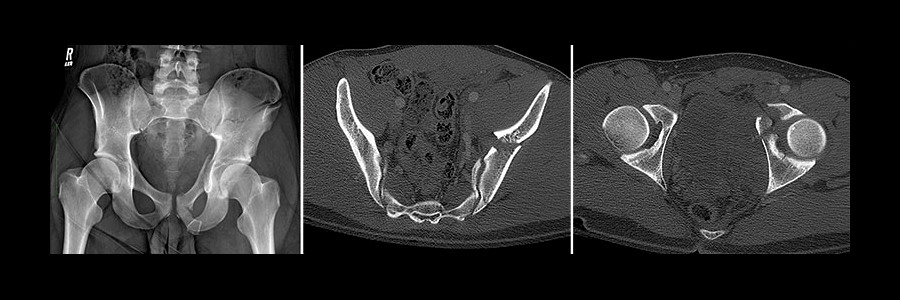

Illustrated X-ray showing severe fractures of the pelvis